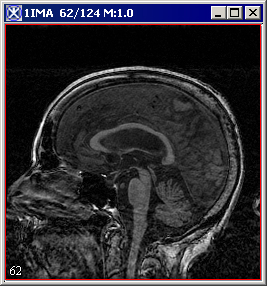

The algorithm begins to run, and a status window appears. When the algorithm finishes, the resulting image appears as an unsigned byte mask in a new image window as shown in Figure 3.

Figure 3. The original image and its unsigned byte mask with detected edges